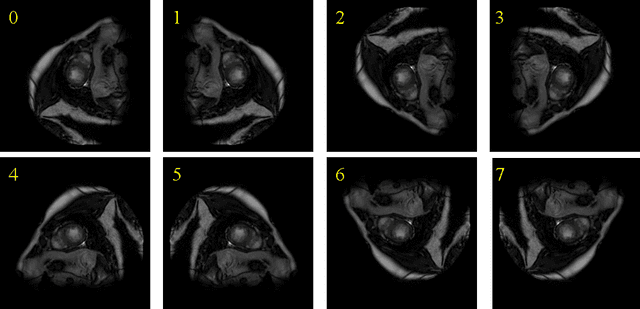

Abstract:In this paper, the problem of orientation correction in cardiac MRI images is investigated and a framework for orientation recognition via deep neural networks is proposed. For multi-modality MRI, we introduce a transfer learning strategy to transfer our proposed model from single modality to multi-modality. We embed the proposed network into the orientation correction command-line tool, which can implement orientation correction on 2D DICOM and 3D NIFTI images. Our source code, network models and tools are available at https://github.com/Jy-stdio/MSCMR_orient/